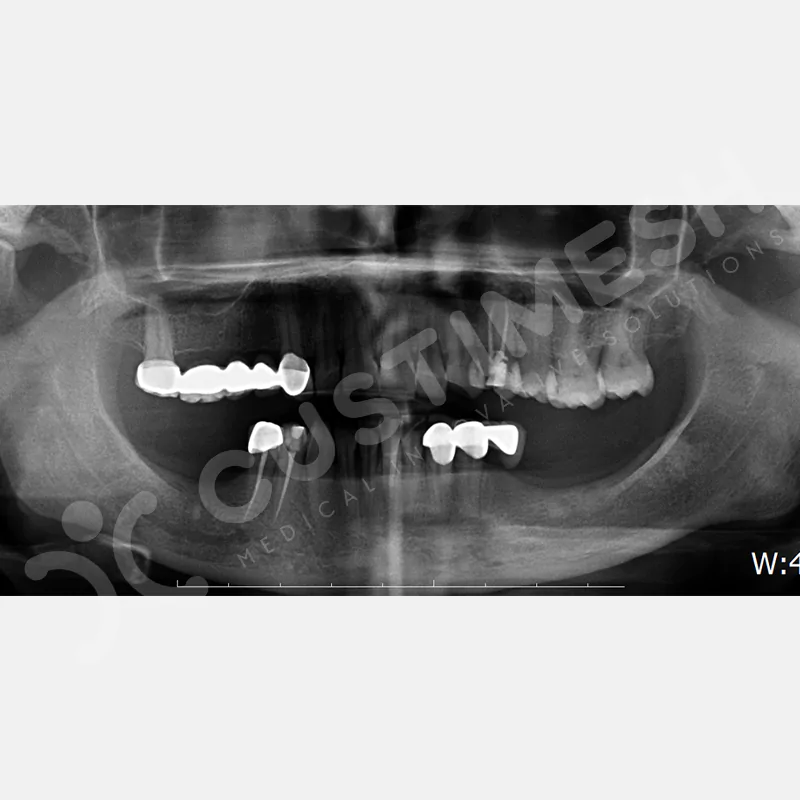

VAKA 1

VAKA 2

VAKA 3